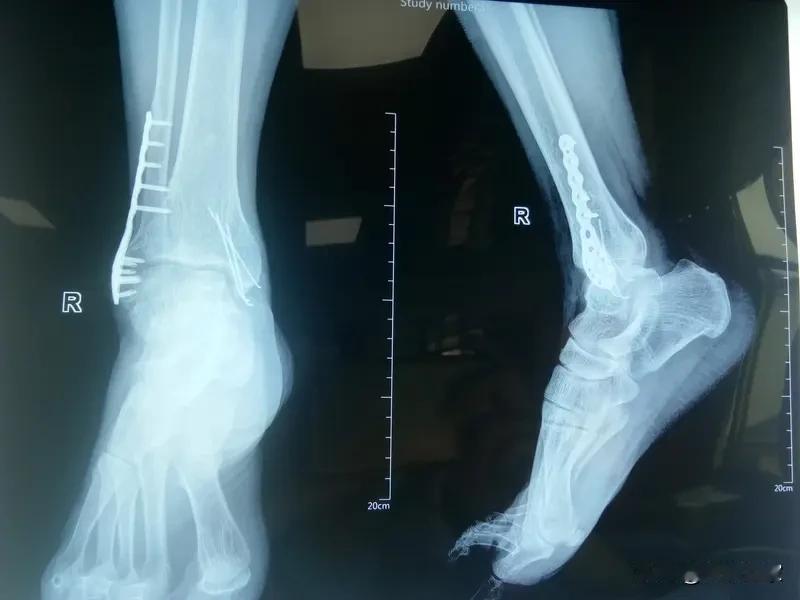

手术做完了,疼却一直没停,多次复查都说正常,你能想象这背后藏着怎样的惊人真相吗?原来在湖南祁阳,有患者在2025年3月11日做踝关节切开复位钢板内固定术时,钻头断裂遗留在了体内。而且据报道,同一病房两名患者同一天手术都出现了这情况。 好在官方介入调查,患者恢复良好,也和院方达成了和解。但诊疗中违反医疗制度这事儿,实在让人捏把汗。官方表示要追责并加强管理。 这事儿你怎么看?医疗安全该如何保障?医院监管又该如何加强? 手术后巨疼 为什么总受伤 陈旧踝关节骨折 踝关节后遗症 手术后巨疼 为什么总受伤 陈旧踝关节骨折 踝关节后遗症 踝关节损伤 手术后不痛 踝关节紊乱